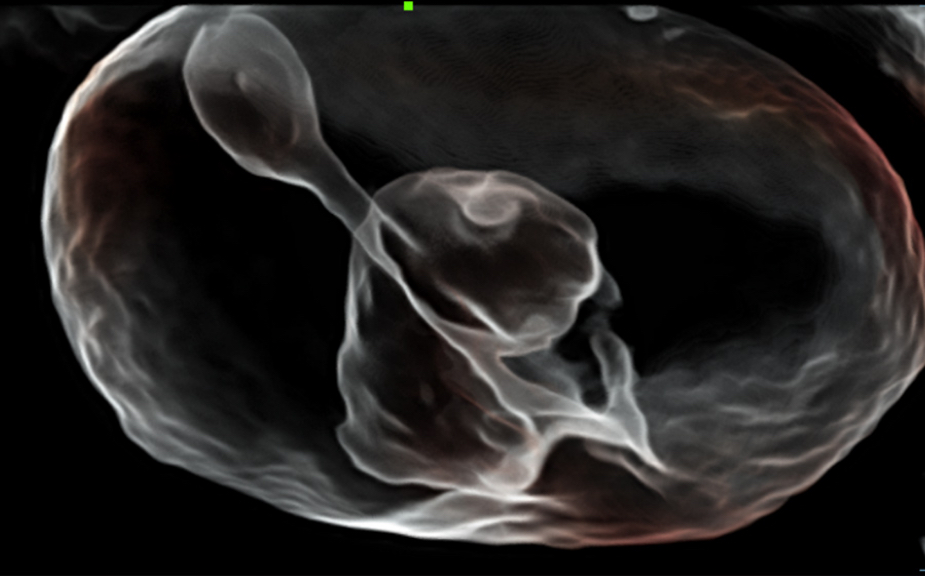

Obrazy kliniczne